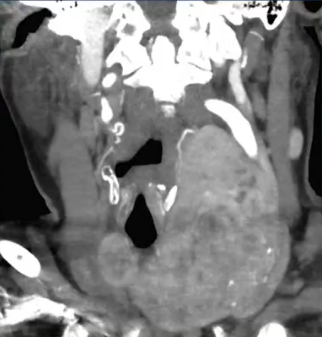

70岁女性,毒性多结节性甲状腺肿导致进行性难治性吞咽困难、窒息发作和呼吸困难

初始甲巯咪唑治疗控制甲状腺功能亢进,但进行性呼吸困难,随后放射性碘生化结果:失败-重新启动甲巯咪唑。影像学结果:缩小不明显,临床结果:咳嗽导致吸入性肺炎,现难治性症状经内分泌科、耳鼻喉科、胸外科、介入放射和影像学评估